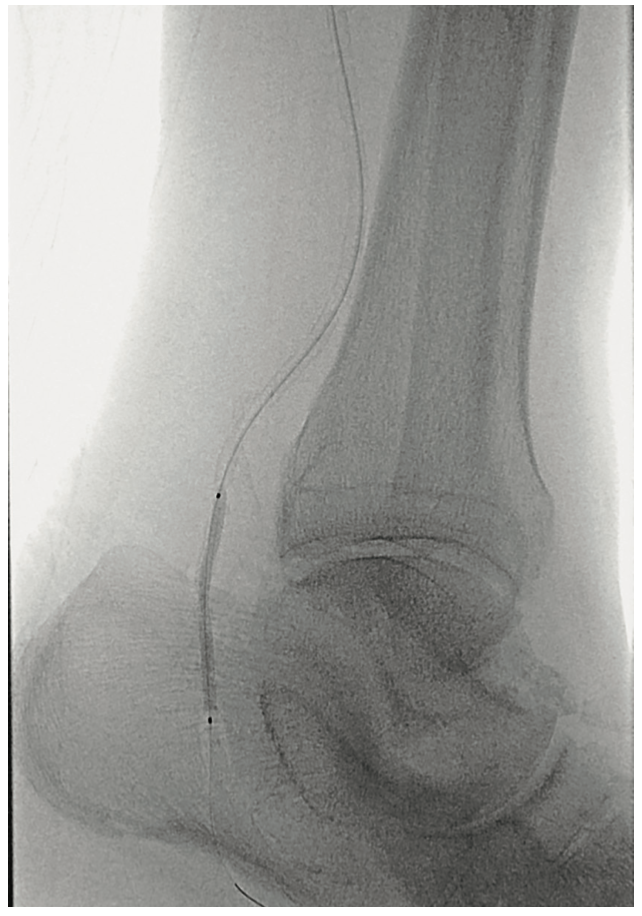

The patient was heparinized. A long 6 French Destination sheath (Terumo Interventional Systems) was used to cannulate the femoral-popliteal artery with an .035-inch system. We then selectively cannulated the posterior tibial artery with an .014-inch Grand Slam wire (Asahi Intecc). Using an .014-inch catheter and wire, we were able to pass through the distal posterior tibial artery stenosis into the pedal vessels. We started with a 2.0 mm plain balloon (POBA), resulting in recoil (Figures 3-4). We then used a 2.5 mm diameter Serranator PTA Serration Angioplasty Balloon (Cagent Vascular) (Figure 5) and achieved significant lumen gain without recoil. The peroneal artery lesion was also treated with angioplasty. The posterior tibial artery was considered to be the most important for wound healing, as the peroneal artery mostly terminated at the ankle level and the posterior tibial artery had strong dominant flow into the left foot. In addition, the anterior tibial and dorsalis pedis pathway was chronically occluded and essentially clinically nonexistent.